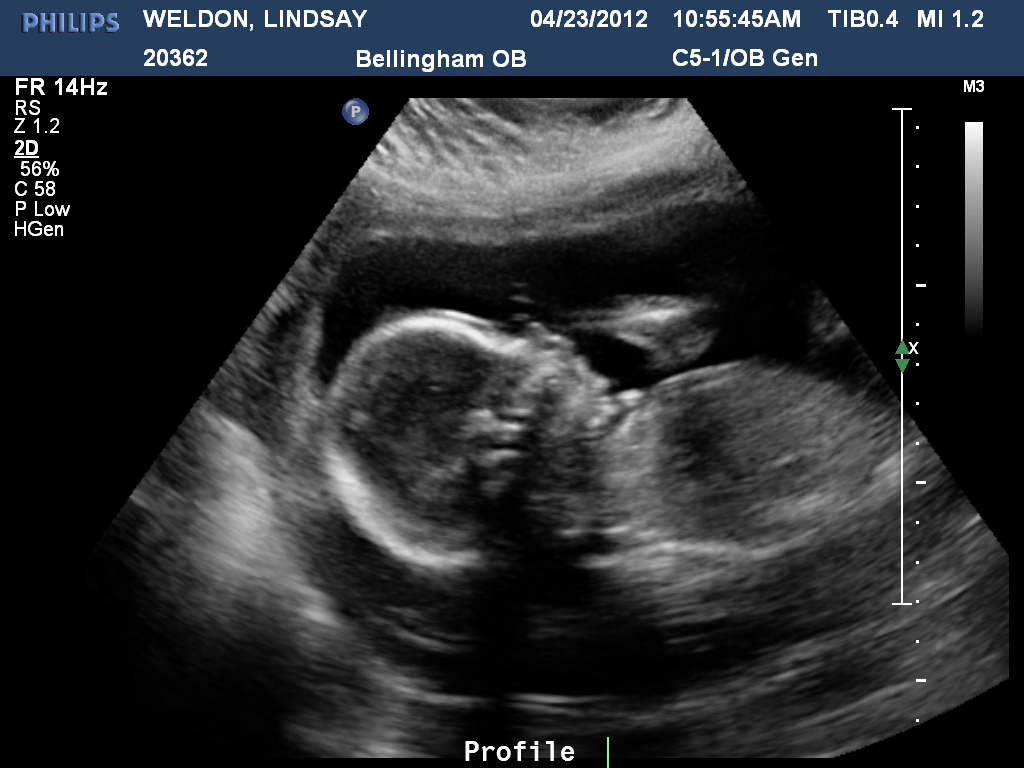

We were able to see our beautiful baby in an ultrasound this morning.

It's a BOY...and we've named him Max.

So, here's some pictures of him:

We love him already...and Enoch is happy to be a big brother. After the ultrasound, he said he asked where his brother was because he wanted to talk to him. AWE, so sweet! Max is due September 6, 2012! (He's measuring at 21 weeks...not 20, so, I really hope he comes a week earlier.)